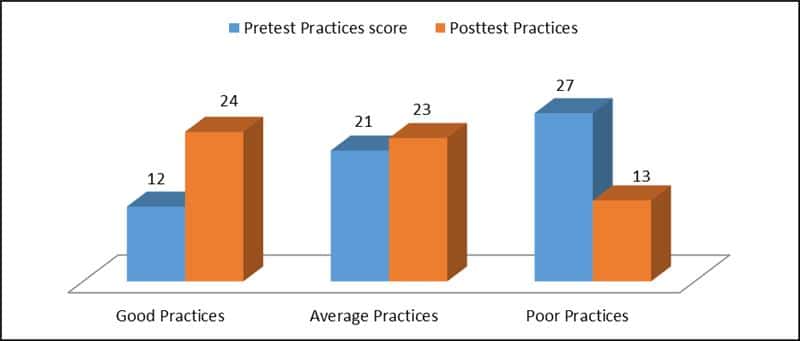

Knowledge, Perception, and Practice of Oral Hygiene Among Undergraduates in a Private University in Ogun State

Background: Oral hygiene practices among undergraduate students are vital for overall health and well-being. This study aims to assess the...Read More